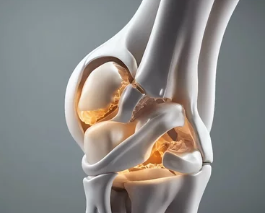

6. 퇴행성 관절염 관리 및 치료법

치료 방법 설명

| 약물 치료 | 진통제(타이레놀), NSAIDs(비스테로이드 항염제), 관절주사 |

| 물리치료 및 운동 | 무릎 근력 강화, 수중 운동, 걷기보다 실내 자전거 추천 |

| 체중 감량 | 체중 1kg당 무릎에 가해지는 하중 4kg 감소 효과 |

| 보조기구 사용 | 무릎 보호대, 지팡이, 깔창 등 |

| 주사 치료 |

- 히알루론산 주사: 관절 윤활

- 스테로이드 주사: 염증 조절 (단기)

- 프롤로주사, DNA 주사 등도 보조적 사용 | | 수술 |

- 연골 성형술, 인공관절 수술(TKR)

- 말기 환자 또는 기능장애 심할 때 고려

결론 요약

- 퇴행성 관절염은 연령 증가, 과체중, 반복적 관절 사용 등이 원인이며

- 통증, 관절 뻣뻣함, 운동 제한이 대표 증상입니다.

- 초기엔 보존적 치료로 충분히 관리 가능하나, 말기엔 수술 고려 필요

- 조기 진단과 근력 유지, 체중 관리가 가장 중요한 예방과 치료의 열쇠입니다.